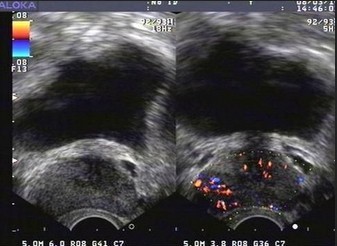

图:前列腺钙化检查影像图